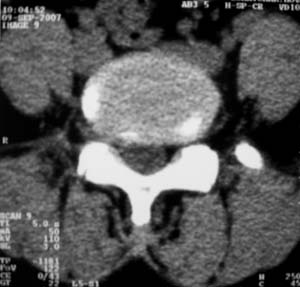

对比观察

[emb10]为什么说是椎间盘病变呢?还有椎间盘脱出有脱向头端方向的吗?

神经源性肿瘤可能性大;1椎间孔较对侧明显大,2相应层面似见椎间盘边缘.建议作mri.

腰间盘突出是有的,右侧椎间孔增大,还是做个mri吧。

右侧椎间孔显宽,考虑为体位不对称所致.扫描层厚偏厚了,考虑孔间型间盘突出.